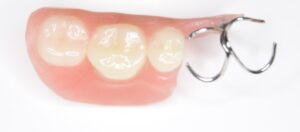

まず、保険のクラスプ義歯がどのような構造かをおさらいします。一般的なクラスプ義歯は、残っている歯に「クラスプ」と呼ばれる金属のバネを引っ掛けて入れ歯を支えます。

抜けた歯を補うために、歯ぐきと同色のプラスチックに人工の歯をつけ、その横に金属のクラスプが付く、という形です。

問題は、クラスプが歯にただ引っ掛けられているだけのため、硬いものを噛むと多少のがたつきが起こり、横からのねじれに弱い点です。

その結果、食べ物が挟まりやすく、噛むたびに支えている歯が揺さぶられます。入れ歯を外すときにも歯がさまざまな方向に揺れるため、歯に負担がかかるのです。